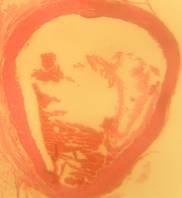

Histopathology

All rats were sacrificed, and their aortas were isolated for histological preparation. The aorta samples were fixed in 10% formaldehyde solution, and their slides were prepared. The slide preparations (6-8 µm thickness) were stained with hematoxylin/eosin. Each slide was scored based on the aorta conditions. The scores ranged from 0–4 with the following criteria: 0 normal condition; 1 if elastic fibres thickening was found; 2 if elastic fibres fragmentation, some foam cells, and fibrosis were found; 3 if smooth muscle proliferation was found, and 4 if plaque ulceration or plaque lipid calcification was found [10].

Morphological structure of aorta’s rats

Aorta’ slide was made every week for one month. Each group of the rats was killed, and the aorta’s rat was observed. From the morphological structure of aorta’s rat, atherosclerosis was scored as follows: on 4 point: 0, normal; 1, widening of elastic fibers with few foam cells; 2, fragmentation of elastic lamellae with numerous foam cells and fibrosis; 3, smooth muscle cells proliferation, medial lipid infiltration and fibrosis; 4, lipid-calcic plaque or ulcerated plaque [10].

The rats (n=4) from each group were sacrificed every week to observe the morphological structure of the aortas. From the lesions, it showed that AND could help chance severity aortic atherosclerosis. The score varied from group A1 until group A4. The aorta morphology of group A1 showed that one aorta had a widening of elastic fibers with few foam cells (score 1) and three aortas had the proliferation of smooth muscle cells (score 3) (fig. 5 A1). AND administration for four weeks could repair aorta condition. Group A4’ aorta morphology showed that three aortas became normal (score 0) and one aorta still had a widening of the first interlamellar (score 1) (fig. 5 A4). Atorvastatin administration could also help changing the severity of aortic atherosclerosis. The score also varied from group B1 until group B4. The aorta morphology of group B1 showed that one aorta had a widening of elastic fibers with few foam cells (score 1), two aortas had fragmentation of elastic lamellae with numerous foam cells and fibrosis (score 2), and one aorta had the proliferation of smooth muscle cells (score 3) (fig. 5 B1). Atorvastatin administration for four weeks could improve aorta condition. Group B4’ aorta morphology showed that two aortas became normal (score 0) and two aortas still had a widening of the first interlamellar (score 1) (fig. 5 B4). Contrarily, the morphological structure of atherogenic rats was getting worse week by week.

Fig. 5: Morphological structure of aorta in albino Wistar male rats 40x. A1, A2, A3, A4 is morphological structure of aorta’s AND rats fed atherogenic diet for 2 mo and continuing with AND for 1 w, 2 w, 3 w and 4 w; B1, B2, B3, B4 is morphological structure of aorta’s atorvastatin rats fed atherogenic diet for 2 mo and continuing with atorvastatin for 1 w, 2 w, 3 w and 4 w; C1, C2, C3, C4 is morphological structure of aorta’s rats fed atherogenic diet for 9th week, 10th week, 11th week, 12th week; D1, D2, D3, D4 is morphological structure of aorta’s rats fed regular diet for 9th week, 10th week, 11th week, 12th week. Black circle (O) = score 1; green circle (O) = score 2; red circle (O) = score 3; blue circle (O) = score 4